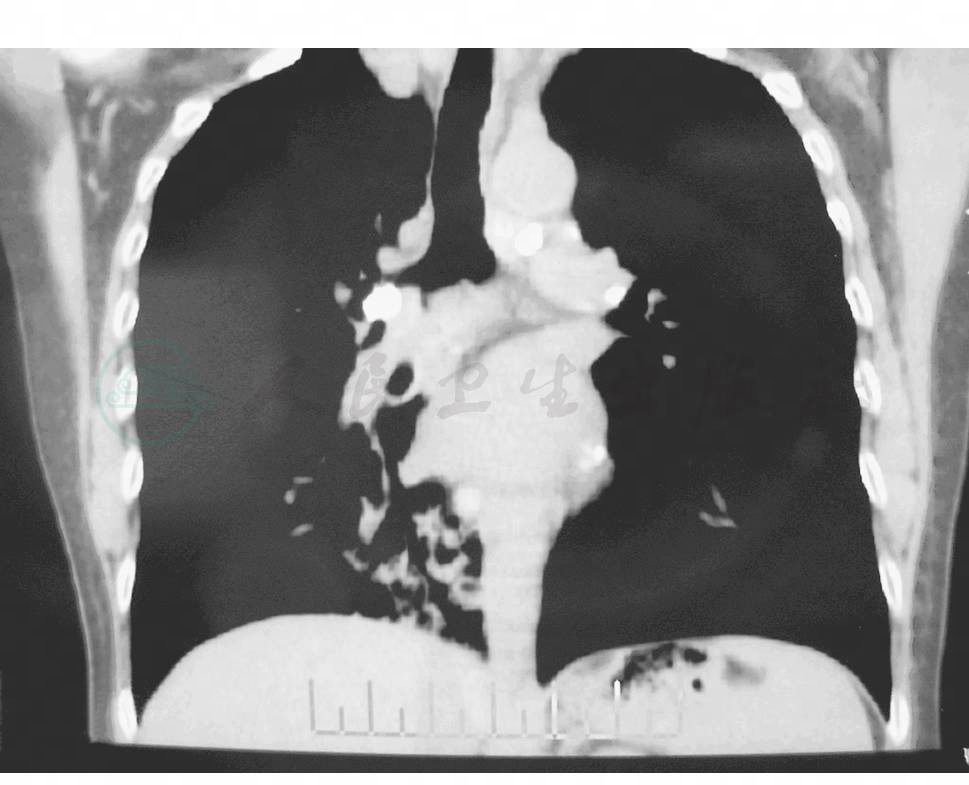

胸部X线检查可表现为纵隔肺门区斑点状钙化影,部分钙化影可位于支气管走行区域。胸部CT:透壁型结石表现为支气管壁内小圆形高密度影突入管腔内;腔内型结石可表现为支气管腔内的斑点状或小棒状高密度影,边缘光整,可堵塞管腔(图2)。

图2 气管支气管结石病的胸部CT表现

注:右中间支气管可见有类圆形高密度影从管壁向管腔突入。